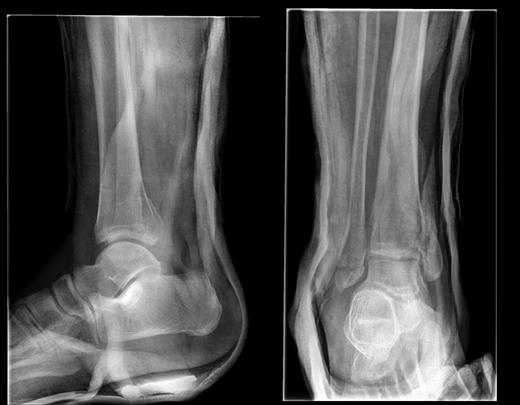

The fracture was unstable and required fixation, but due to extensive soft tissue damage and swelling and a lack of sickle cell testing, the operation was delayed for 6 days (Fig. 2). The operation was performed under a General Anaesthetic with Popliteal Block with the patient supine and a sandbag placed under the right buttock. A tourniquet was applied and a lateral approach to the fibula was taken with standard washout and fracture reduction achieved. The distal fibular fracture was fixed using three partially threaded cancellous screws.

The distal tibia was approached via a direct medial approach. This revealed an extensively comminuted fracture extending proximally. The fracture site was identified, reduced and held in place with 2 × 2.0 mm k-wires. This medial fracture was not amenable to screw fixation or tension band wiring; an LCP plate was applied which did not have an adequate fit. A four-hole medial distal tibial LCP was not available. The next alternative was to use a PHILOS plate as it appeared to fit the contours appropriately. An intraoperative decision was made to use a 3.5 mm LCP® Proximal Humerus Plate (PHILOS) plate. The plate fit the distal tibial contours well once the fracture was reduced. Three proximal non-locking cortical screws and multiple distal locking screws were applied producing a stable construct (Fig. 2).